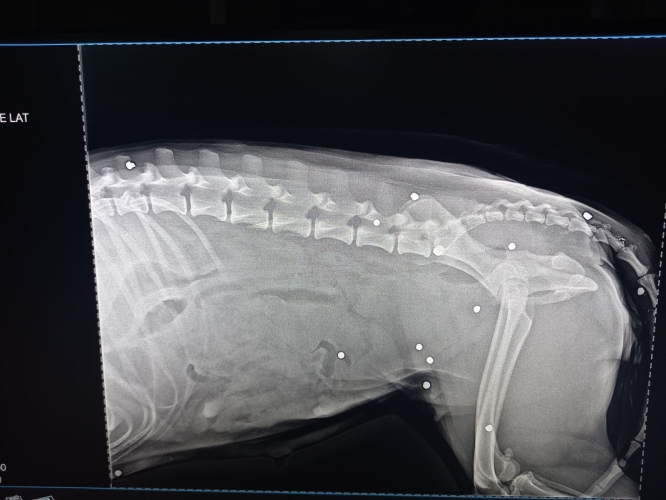

Оренбурженка связалась с волонтёрами приюта "Я - Живой". Удалось найти автомобиль, свозить животное в ветклинику. Как оказалось, её расстреляли из охотничьего ружья. В теле обнаружили 19 дробин. Не было практически ни одного живого места: повреждены голова, лапы, позвоночник, грудь, горло, живот, глаз. Врач отметил, что если бы стреляли с более близкого расстояния, то шансов выжить у бедной собаки не было бы...

Кроме того, собака была беременна. Щенков она потеряла. Белоснежку, как назвали пострадавшую собаку, ждут операция и длительное восстановление.

Вопрос об операции будет решаться после того, как ее состояние стабилизируется, ей нужно отогреться, так как два дня она пролежала в снегу, проколоть антибиотики, подождать сокращения матки и остановки кровотечения. Одно точно: левый глаз, залитый кровью, видеть не будет, дробь повредила его полностью, - отметили волонтеры.